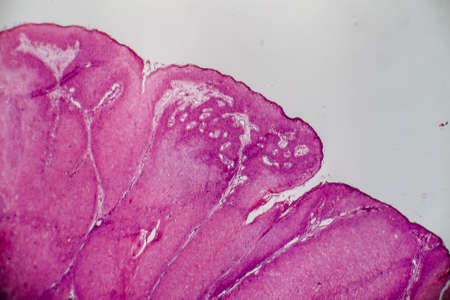

Bowen's Disease Tumor under the microscope 100x

Bowen's Disease Tumor under the microscope 100x